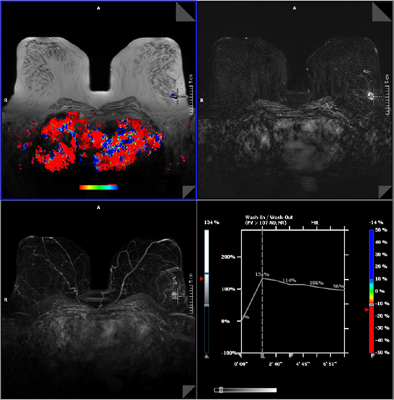

A Siemens Healthcare új leletező szoftvert kínál, amely megkönnyíti a radiológusok számára a diagnózist és a biopsziát. Ezzel új lehetőségek nyílnak meg az MR-tomográfia nőgyógyászati alkalmazása előtt. A Syngo BreVis leletező szoftver egy páciens valamennyi vizsgálati eredményét – így például az MR-kép mellett ultrahang- és röntgenképeket is – egy pillantással áttekinthető képernyőben egyesíti. Ez a technika eddigi szintjén nem volt lehetséges. Továbbá, a Syngo BreVis Biopsy nevű, ugyancsak új intervenciós szoftver segítségével a vizsgáló orvos szükség esetén rögtön a biopsziát is megtervezheti illetve végrehajthatja. Ez messzemenően automatikus vezérléssel és az eddiginél lényegesen gyorsabban történik, ami páciensnek és orvosnak egyaránt kedvező.

Az MR-alapú emlő-képalkotás fő eszköze jelenleg a Magnetom Espree – Pink emlő-szkenner, amelyhez az alkalmazások széles választéka járul. Ez bővül most a Syngo BreVis és Syngo BreVis Biopsy speciális szoftvermegoldásokkal. Mindkét számítógépes diagnosztikai „tool“ az úgynevezett Syngo-munkahelyek támogatásával működik. A Syngo Brevis Workplace olyan rugalmas hardver és szoftvermegoldás, amely könnyen kezelhető, hatékony leletezést és automatikus vizsgálatijelentés-készítést tesz lehetővé az úgynevezett BI-RADS klasszifikáció alapján. A Syngo Brevis Biopsy Workplace szoftvere automatikusan, gyorsan és pontosan meghatározza a mintavétel koordinátáit. A két új szoftvert a MeVis brémai képalkotószoftver-cég fejlesztette a Siemens-szel való szoros együttműködésben.